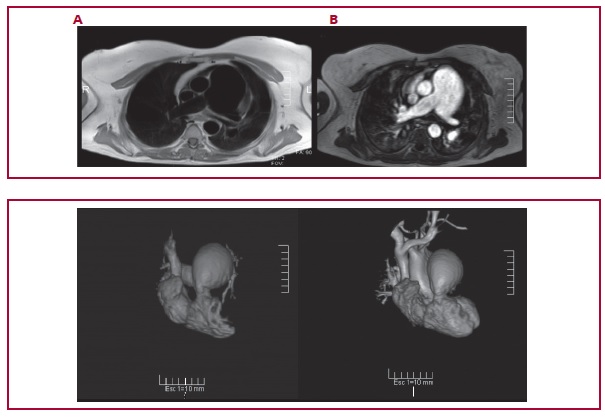

Aneurisma de la arteria pulmonar en un paciente adulto

IMÁGENES EN CARDIOLOGÍA